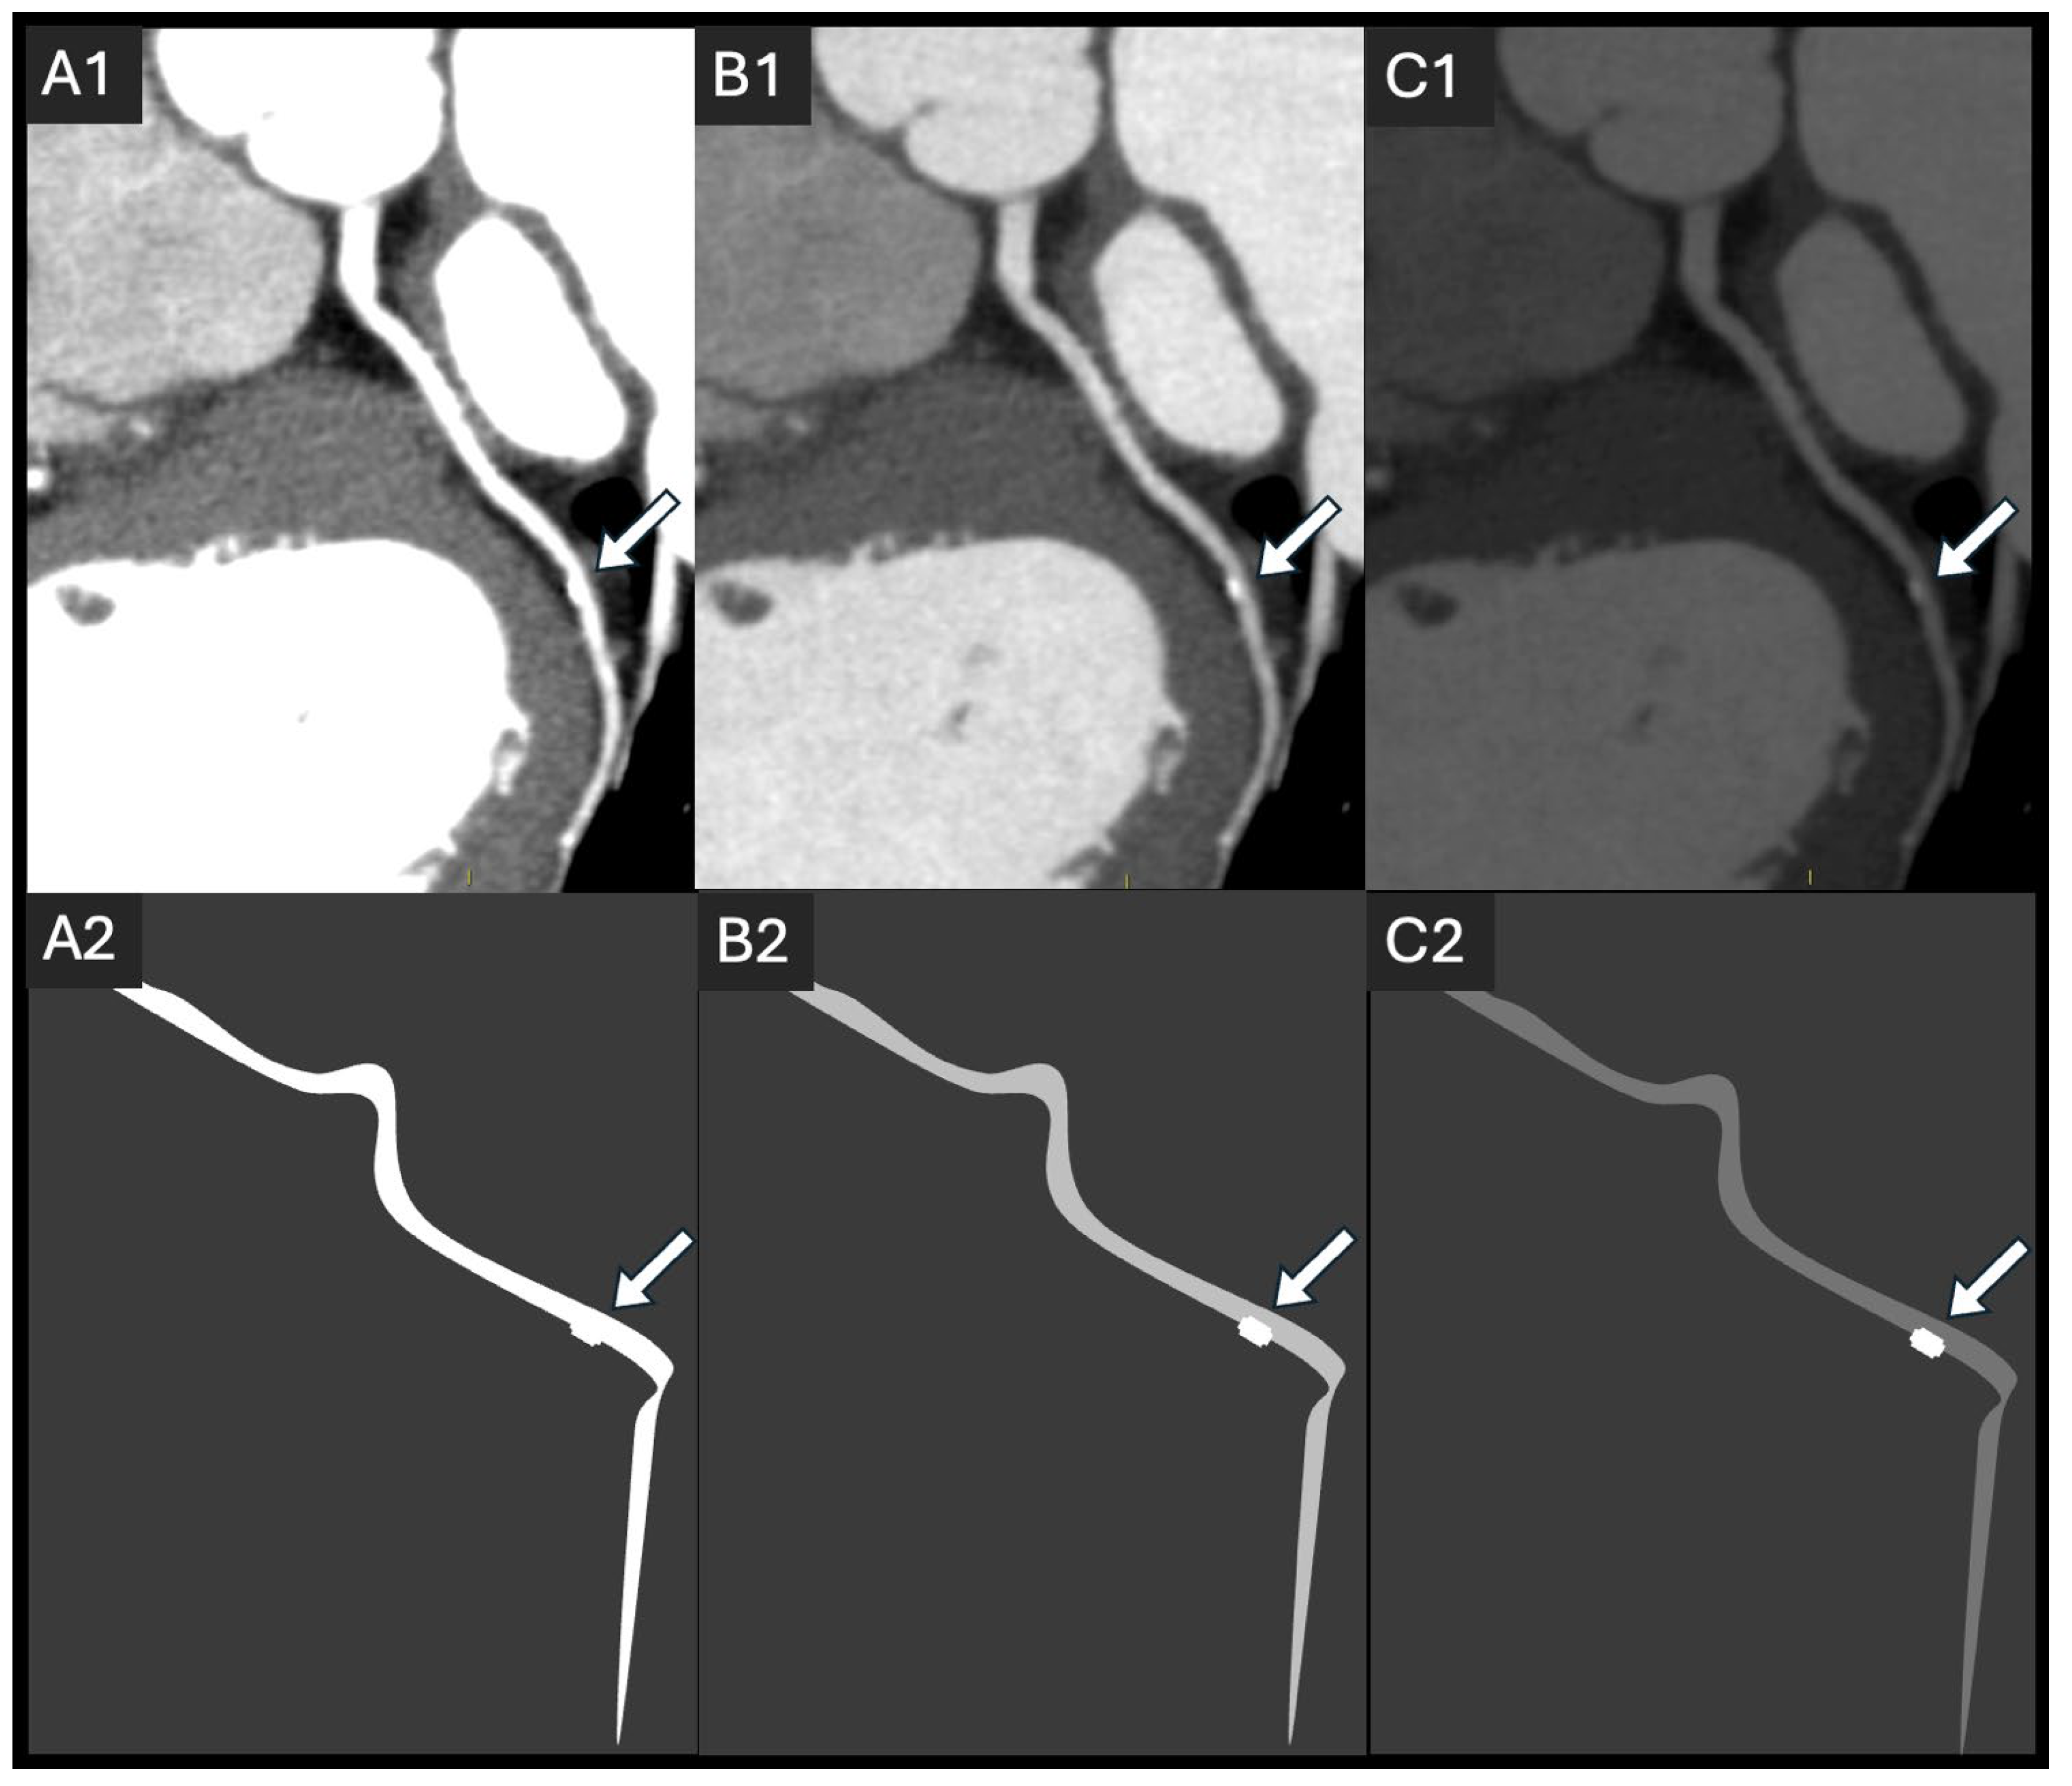

5.3. Iterative and Deep-Learning Image Reconstruction

- Li, W.; Lu, H.; Wen, Y.; Zhou, M.; Shuai, T.; You, Y.; Zhao, J.; Liao, K.; Lu, C.; Li, J. Reducing both radiation and contrast doses for overweight patients in coronary CT angiography with 80-kVp and deep learning image reconstruction. Eur. J. Radiol. 2023, 161, 110736. [Google Scholar] [CrossRef]

- Li, W.; Diao, K.; Wen, Y.; Shuai, T.; You, Y.; Zhao, J.; Liao, K.; Lu, C.; Yu, J.; He, Y. High-strength deep learning image reconstruction in coronary CT angiography at 70-kVp tube voltage significantly improves image quality and reduces both radiation and contrast doses. Eur. Radiol. 2022, 32, 2912–2920. [Google Scholar] [CrossRef]